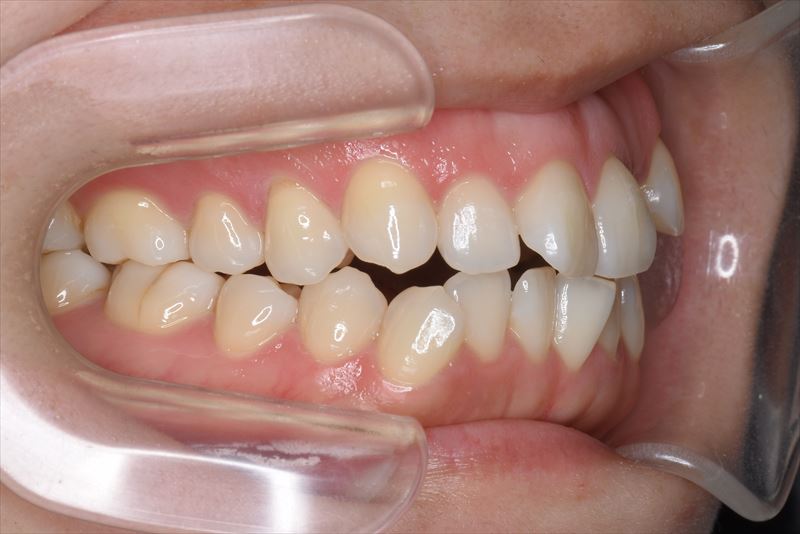

治療前

主な症状

前歯で咬めない。歯が重なっている。

症状

叢生、口唇の突出